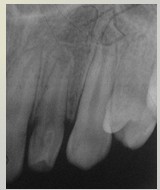

解析: 牙齿异位萌出

牙齿异位萌出的临床表现包括:第一恒磨牙近中边缘嵴阻生于第二乳磨牙远中牙颈下,X线:第二乳磨牙远中根牙颈部吸收区或非典型性吸收,第一恒磨牙近中边缘嵴嵌入;第二乳磨牙间隙开始缩小。治疗措施包括:早期临床观察,钢丝结扎分离,截冠加金属冠修复,拔除第二乳磨牙,导萌器引导恒牙萌出。

解析: 低位乳牙-下沉牙,愈着牙

解析: 乳牙滞留